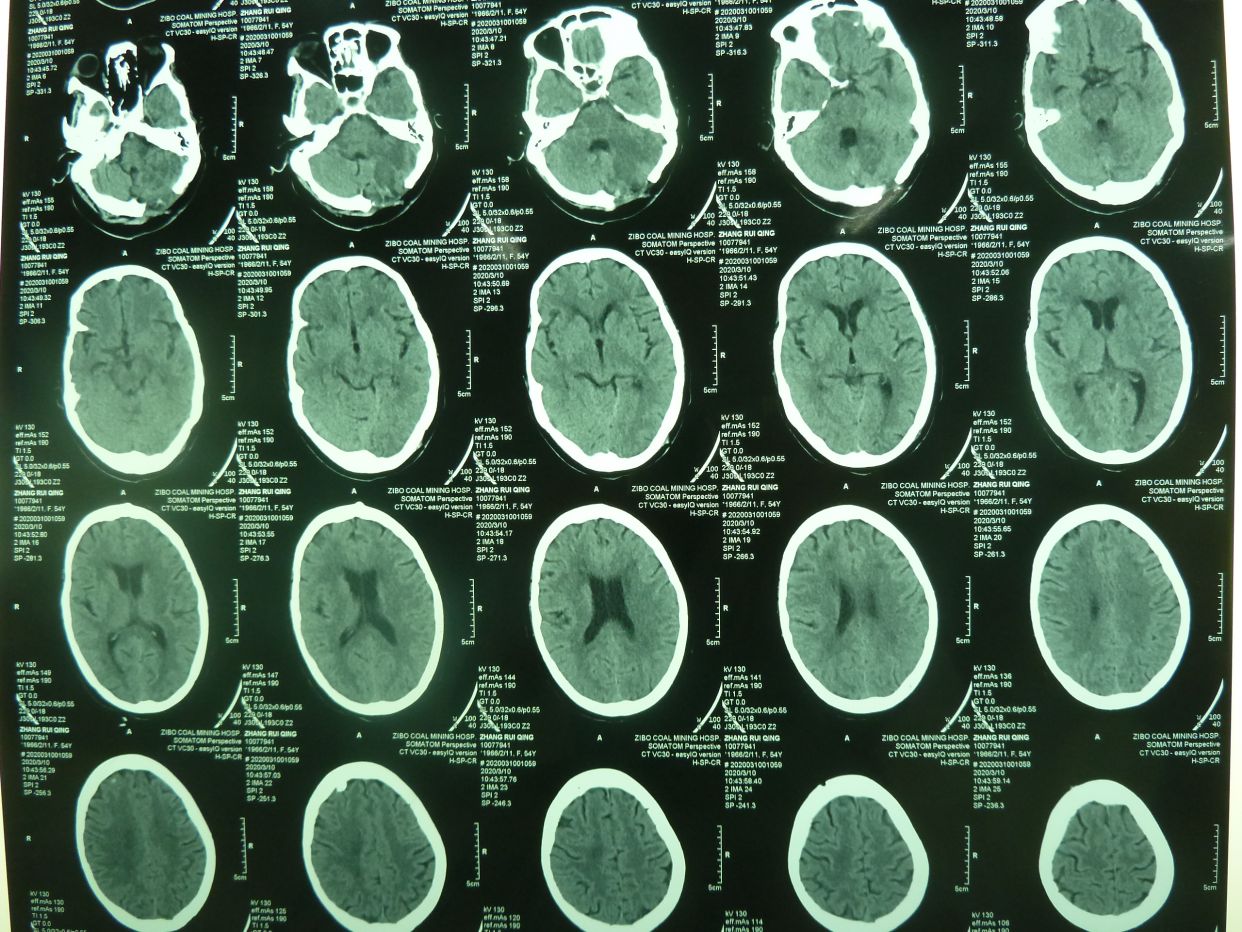

CT示,小脑大量出血破入全脑室并梗阻性脑积水,与家属沟通并签字后急症行脑室外引流术,后颅凹开颅血肿清除术。

术后1天CT复查示,血肿清除满意,基底池可见,患者刺激睁眼。

患者术后1月,神志清,正确回答问题,四肢话动良好,出院康复。